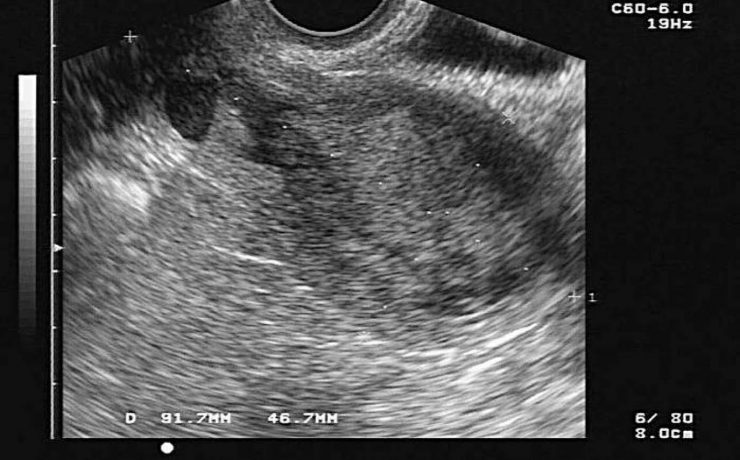

El incremento de la obesidad, del síndrome metabólico y su subsiguiente manifestación hepática, el hígado graso no alcohólico, se ha convertido en una enfermedad muy común en la práctica médica. El desarrollo de los conocimientos sobre el NASH se basa en la teoría inicial de los dos golpes o momentos.